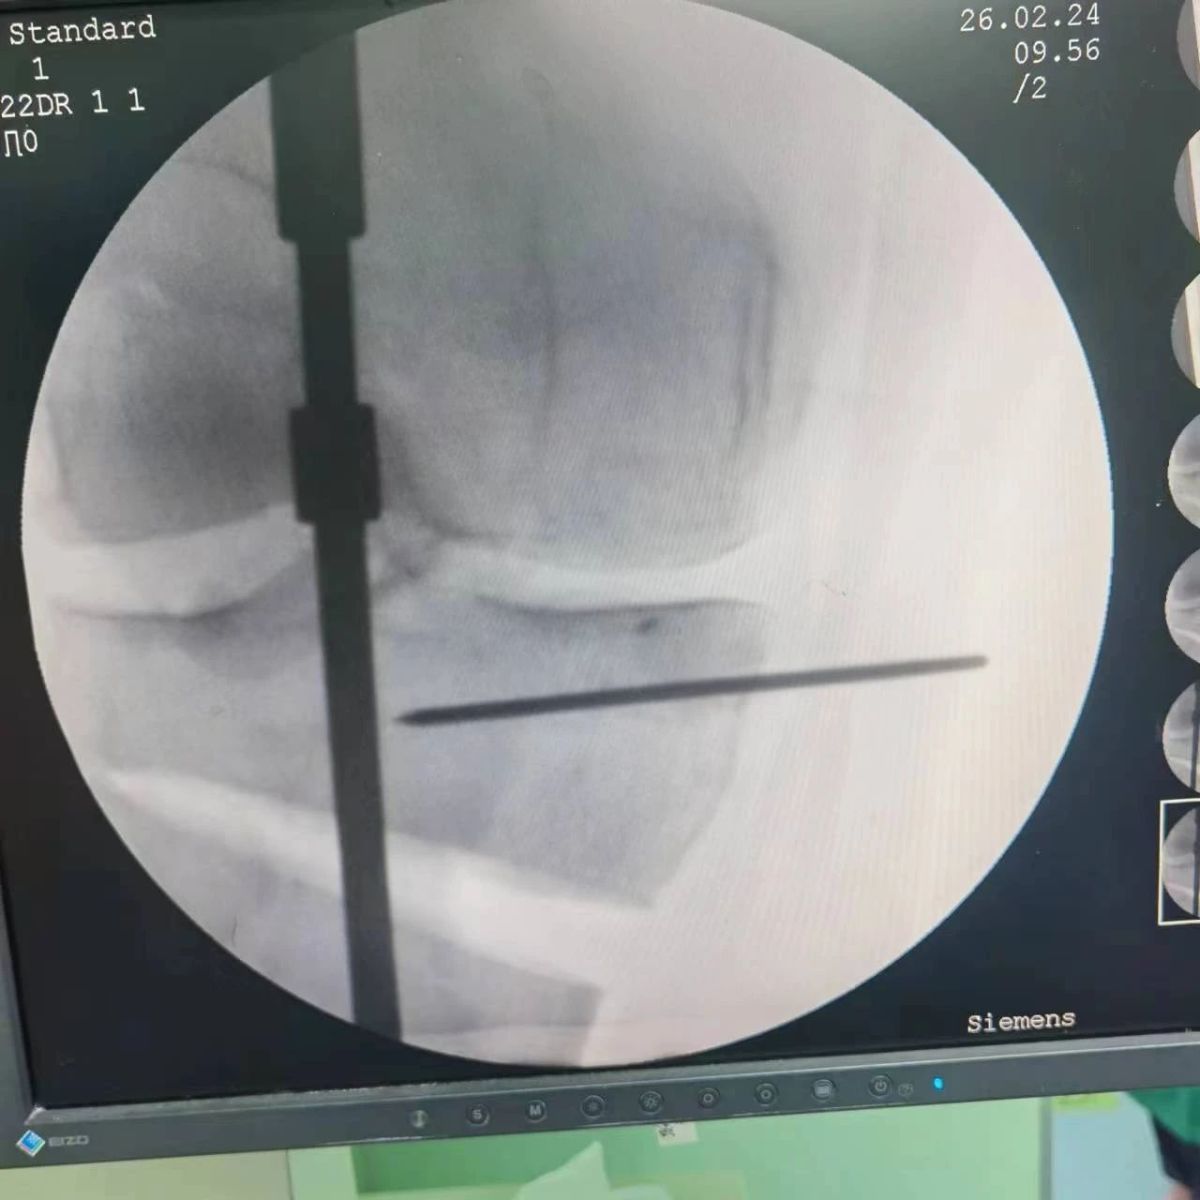

2月26日,漯河市骨科醫院(漯河醫專二附院、漯河市立醫院)膝關節外科、運動損傷科(骨六科)在保膝治療方面取得了新的突破,李付彬主任帶領岳龍等團隊醫師,順利完成“計算機精準術前規劃聯合3D打印截骨導板輔助脛骨高位截骨治療膝關節骨性關節炎”的手術,這在漯河市尚屬首例!

患者為一名45歲男性,查體及X片可見明顯的膝內翻,內翻畸形主要來源于脛骨近端,關節鏡下可見內側間室軟骨全層磨損,疼痛較重,年紀輕輕幾乎喪失工作能力。對于這種日?;顒有枨蟊容^大的患者朋友,我們盡最大可能給予保膝治療,李付彬主任給患者詳細講解了保膝治療的方案(脛骨近端高位截骨)及預期效果,給患者帶來了極大希望。為了更精確、更微創的治療,李付彬主任團隊緊跟國內外科技前沿,采用計算機精準術前規劃,并設計3D打印截骨導板,力求給患者帶來更精準、更安全的手術效果。

李付彬主任團隊通過精準術前規劃,設計目標力線及調整撐開角度,轉化成需要撐開的高度,最終設計出同等高度的填充塊,術中驗證力線調整與術前規劃完全一致!

鋼板位置、螺釘位置及長度均可通過術前規劃計算,術中通過定位操作,基本與術前規劃一致,手術快速高效完成,外側合頁保留完整。無任何并發癥出現。術后見鋼板位置及力線糾正近乎完美!

OWHTO手術效果依賴于多個數據參數,比如:截骨的入點、合頁位置的選擇、截骨線的深度、截骨線的方向、撐開的距離等,依托計算機術前精準規劃和3D打印導板可輔助醫生精準控制上述參數,使截骨更準確,真正達到精確的力線調整,減少術中透視次數,縮短手術時間并降低手術風險,從而使得OWHTO得到更好的應用,造?;颊?。